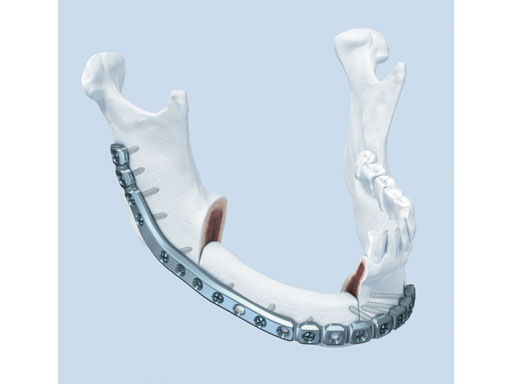

The preformed plates provide a 3-D shape which is based on the statistical analysis of mandible models obtained from over 2,000 CT scans, originating from various adult populations in collaboration with Marc C Metzger (Freiburg, Germany) who had already played a crucial part in developing the preformed orbital plate from the matrix orbit system.

Fig 1 Preformed reconstruction plate.

The plates are available in three sizes: small, medium, and large with each plate offering a section of increased strength in the body and angle regions. The anatomical shape of the preformed reconstruction plates also allows for transoral application, ie, in combination with transbuccal instrumentation and/or the 90 screwdriver. The minimal intraoperative bending that is required preserves the optimal threaded-hole shape, especially in the preformed sections. These features result in a plate with increased fatigue life compared to standard reconstruction plates, thus reducing the risk of plate failure.